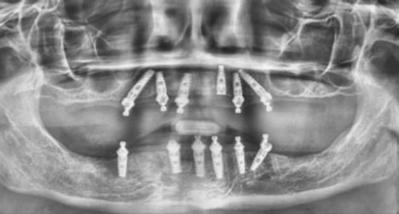

Figure 3: Preoperative panographic view of the maxillary and mandibular arches from the CBCT scan demonstrating anatomy that will impact implant placement Figure 4: Extraoral scan of the full maxillary and man dibular dentures that patient presented with, which she was unable to wear due to a significant gag reflex Figures 5A and 5B: Virtual planning of implant placement in the maxillary arch Figures 6A and 6B: Virtual planning of implant placement in the mandibular arch

A CBCT scan was taken and panoramic views of the maxilla and mandible evaluated (Figure 3). Bilateral pneumatization of the maxillary sinus was noted, but adequate bone height was present between the premolars for implant placement to support an All-on-X hybrid prosthesis. In the mandibular arch, sufficient height was available between the mental foramen bilaterally and over the inferior alveolar nerve for implant placement to also sup port an All-on-X fixed hybrid prosthesis. A discussion was held with the patient that implants could be placed in both arches that would allow restoration with fixed prosthetics. Should sufficient insertion torque be achieved at the time of implant placement, a screw-retained hybrid provisional prosthesis would be placed and worn for several months during healing after which a final prosthesis would be fabricated. The patient would also be able to do a “trial-run” of the esthetics with the provisional prosthesis, with any requested modifications made when the final prosthesis was designed and fabricated. The treatment plan included six implants in each arch to support the planned hybrid prosthe ses. The patient was informed that reduction of the crestal bone would be required to achieve a flat ridge for adaptation of the prosthesis to the ridge as well as to provide adequate interarch space for the final prosthesis. The patient accepted the treatment plan. An intraoral scan of the arches was performed with Medit i500 (Medit Corp, Seoul, Korea) as well as the current complete arch maxillary and mandibular dentures (Figure 4). The patient was dismissed and scheduled for the surgical appointment.

The scans were imported into the planning software (Real GUIDE™, Allston, Massachusetts) and merged with the CBCT scan to allow implant planning. The maxillary arch was planned for implants at six sites, including tilted implants mesial to the maxillary sinus bilaterally to avoid the need for sinus augmen tation and allow more distal placement of the implant platform for a better anterior/posterior (A-P) spread (Figure 5A). ULT implants were planned as follows: No. 3 (3.75 x 11.5 mm), No. 6 (3.75 x 11.5 mm), No. 8 (3.75 x 11.5 mm), No. 9 (3.75

The mandibular arch was then planned for seven possi ble implants with the extra implant beyond what was initially planned should the short posterior implant on the patient’s left have less than ideal initial stability to provide better stability of the provisional prosthesis (Figure 6A). Ditron Dental ULT implants were planned as follows: No. 19 (3.75 x 11.5 mm), No. 20 (3.75 x 11.5 mm), No. 22 (3.75 x 11.5 mm), No. 24 (3.75 x 11.5 mm), No. 25 (3.75 x 11.5 mm), No. 27 (3.75 mm x 10 mm), and No. 30 (3.75 x 11.5 mm) (Figure 6B). A replica of the current dentures was fabricated to be used as a surgical guide, and the center of the replica was removed with a lab bur to create a zone for the implants to emerge to ensure they would be within the proper prosthetic zone (Figure 7).

The patient presented for surgery, and the consent form was reviewed and signed. IV sedation was initiated, and local anes thetic (2% Lidocaine with 1:100,000 epi) was administered in both arches. A crestal incision was made in the maxillary arch midcrest, and a full thickness flap was elevated to expose the buccal and palatal aspects of the ridge. Evaluation of the osseous ridge noted it was fairly flat, and reduction was deemed to be not necessary. The surgical guide was inserted and utilized to guide the location of the osteotomies. ULT implants were placed at the six planned sites: No. 3 (3.75 mm x 13 mm), No. 6 (3.75 mm x 10 mm), No. 8 (3.75 mm x 10 mm), No. 9 (3.75 mm x 11.5 mm), No. 11 (3.75 mm x 10 mm) and No. 14 (3.75 mm x 13 mm). Insertion torque of greater than 40 Ncm was achievable at five of the sites with site No. 10 being less than 30 Ncm and insuf ficient to support an immediate load. As sufficient A-P distance and adequate insertion torque was present utilizing the five other maxillary implants, it was decided to place an immediate provi sional hybrid prosthesis. Multi-unit abutments (MUAs) with the following angulations were placed: (No. 3 = 30 degrees, No. 6= 17 degrees, No. 8= 0 degrees, 11 = 17 degrees, and No. 14 = 30 degrees). The soft tissue was repositioned around the MUAs, and primary closure was achieved utilizing a continuous polylactic acid (PLA) suture.

Figures 11 and 12: 11. Articulated virtual maxillary and mandibular provisional prostheses. 12. Panoramic view following implant placement, MUA attachment, and insertion of the provisional hybrid prostheses to document the initial clinical presence

A scalpel was then utilized to create a crestal incision in the mandible from the approximate first molar on the right to the approximate first molar on the left, and a full thickness flap was ele vated with identification of the mental nerve and its foramen bilaterally. As with the maxillary arch, the mandibular crestal bone was fairly flat, and ridge reduction was not needed. The surgical guide was inserted in the mandible and utilized to guide the location of the osteotomies. ULT implants were placed at six sites as: No. 20 (3.75 mm x 10mm), No. 22 (3.75 mm x 10m m), No. 24 (3.75 mm x 11.5 mm), No. 25 (3.75 mm x11.5 mm), No. 27 (3.75 mm x 10 mm) and No. 30 (3.75 mm x 10 mm). Insertion torque of greater than 40 Ncm was achievable at all of the sites. As sufficient adequate insertion torque was present, placement of an immediate provisional hybrid prosthesis was planned. MUAs with the following angulations were placed (No. 20 = 30 degrees, No. 22 = 0 degrees, No. 24 = 0 degrees, No. 25 = 0 degrees, No 27 = 0 degrees, and No. 30 = 0 degrees). The soft tissue was repositioned around the MUAs, and white protective caps were placed onto the MUAs. Primary closure was achieved, and a continuous PLA suture placed. The patients’ dentures were relieved to seat over the white caps, and a reline impression was taken with the two arches in occlusion to allow use of the current vertical dimension of occlusion (VDO) in the planned fabrication of the provisional hybrid restorations. The patient was dismissed and scheduled for postoperative check and suture removal in 2 weeks.

Figures 18 and 19: 18. The patient smiling with the full-arch monolithic zirconia hybrid prostheses on the maxillary and mandibular arches. 19. Panorex of the final monolithic zirconia hybrid prostheses on the maxillary and mandibular arches